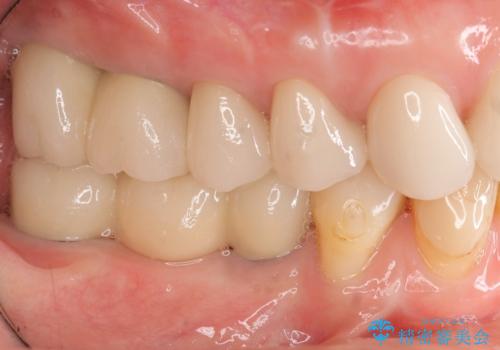

全顎 虫歯 インプラント治療

不適合やすり減ったクラウンを全て除去し、虫歯を丁寧に除去したのち精密なセラミック治療を行いました。

しっかりと調整された咬合関係と、見た目の改善に大変喜んでいただくことができました。